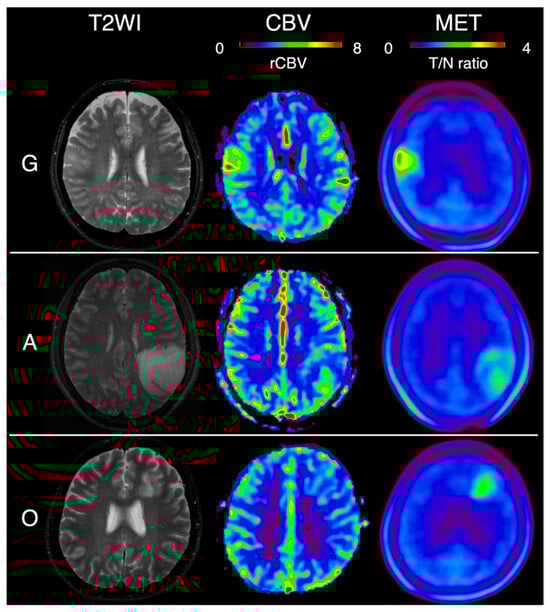

| G | glioblastoma, IDH-wildtype |

| A | astrocytoma, IDH-mutant |

| O | oligodendroglioma, IDH-mutant and 1p/19q-codeleted |